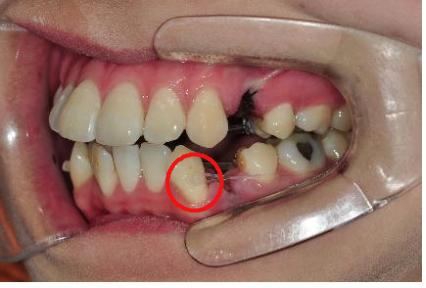

치아교정 장치를 부착한 다음, 철사를 연결합니다~

어떤 부분은 투명한 관에 철사를 넣어 연결해 주시는데요~

전 요거 맘에 들어요 ㅋㅋㅋ 먼가 철사로부터 제 입이 보호되는 것 같아요

안전 장치 같은 느낌 ㅎㅎ

다만 하악 1번치아에 부착된 브라켓으로 혀가 자꾸 쓸리네용 ㅠ.ㅠ

요 부분 때문에 먹을 때랑 말할 때 조금 아프네요.